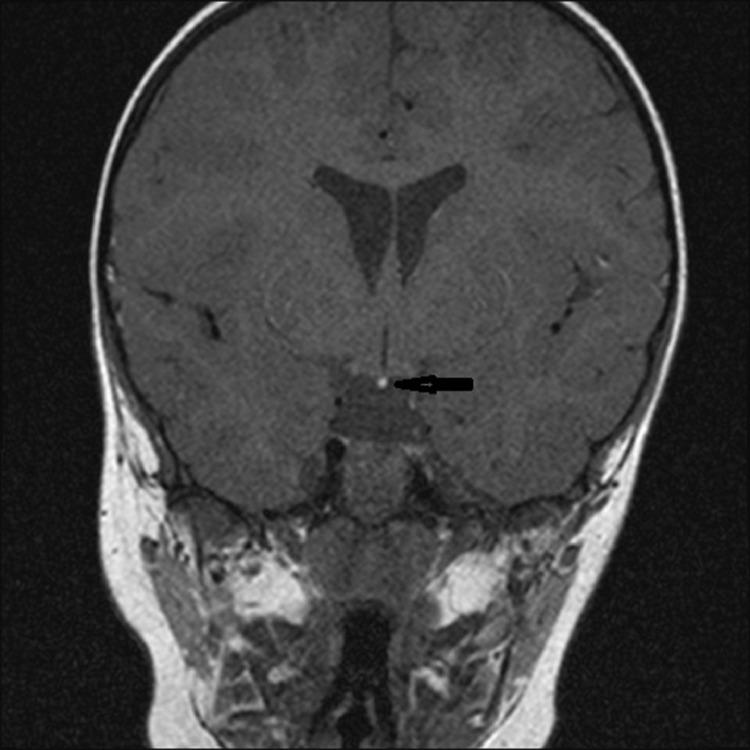

一名男孩的异位神经垂体:病例报告及文献复习

Ectopic neurohypophisis in a boy: A case report and review.

Ectopic neurohypophysis is rare anomaly which is characterized by ectopic location of posterior pituitary lobe (neurohypophysis), pituitary stalk abnormalities and association with dysfunction of anterior lobe related with growth hormone or with multiple dysfunction of the same.We present a rare case of posterior ectopic pituitary and pituitary stalk hypoplasia isolated in 2 year-old male patient.

摘要

异位神经垂体是一种罕见的异常情况,其特征为垂体后叶(神经垂体)异位、垂体柄异常,并伴有与生长激素相关的前叶功能障碍或多种功能障碍。我们报告了一例罕见的2岁男性患者孤立性垂体后叶异位和垂体柄发育不全的病例。